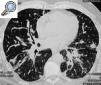

Paciente de 51 años de edad entre cuyos antecedentes tan sólo destacaban hipertensión arterial y dermatitis atópica. Era ex fumador desde hacía 20 años (20 paquetes/año). Acudió por disnea de un mes de evolución. La exploración clínica mostraba escasos crepitantes en ambas bases. En la radiografía de tórax se apreciaba una afectación intersticial bilateral en los 2 tercios inferiores de ambos pulmones, que no se visualizaba en una radiografía realizada 2 años antes que aportó el paciente. Con el diagnóstico de sospecha de EPID se realizó una tomografía computarizada de alta resolución de tórax, en la que se apreciaban las siguientes alteraciones: pequeñas adenopatías paratraqueales derechas, lesión intersticial, de predominio peribroncovascular en la zona central, con engrosamiento de septos interlobulillares en la periferia, engrosamiento irregular de cisuras y áreas de fibrosis en ambas bases. El hemograma, la bioquímica clínica básica y la gasometría arterial fueron normales; los anticuerpos antinucleares, anticuerpos anticitoplasma de neutrófilo, serología virásica y baciloscopia de esputo fueron negativos. Dada la intensa disnea se instauró tratamiento con corticoides orales. Con objeto de aclarar la naturaleza de las imágenes radiológicas se realizó fibrobroncoscopia en la que no se encontraron hallazgos morfológicos, si bien el estudio histopatológico de la biopsia transbronquial demostró la existencia de un adenocarcinoma moderadamente diferenciado con extensa permeación linfática y extensas áreas de fibrosis. Una biopsia pulmonar quirúrgica confirmó el diagnóstico y las características histológicas descritas.

Fig. 1. Afectación intersticial con predomino de intersticio broncovascular y periférico, junto a áreas indicativas de conglomerados fibróticos.